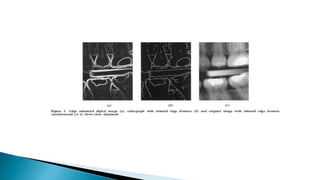

A, Central ray directed at right angle to film positioned parallel to arch. B, Limited information

is gleaned from the radiograph because of superimposition of structures and canals.

Mandibular Molars A, Centralray directed at right angle to film positioned parallel to arch. B, Limited information is gleaned from the radiograph because of superimposition of structures and canals.